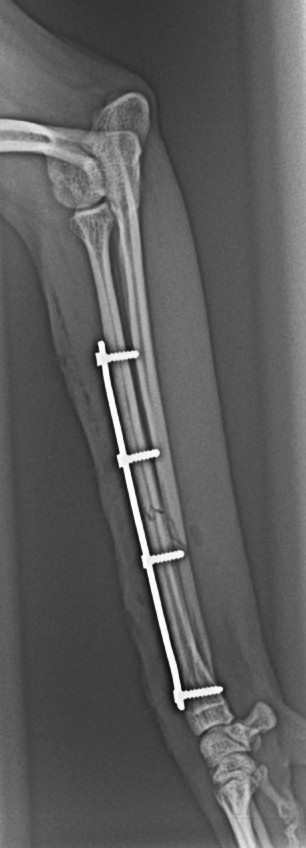

- 骨折(プレート固定等)

・橈尺骨(前肢)骨折整復術 40万円前後